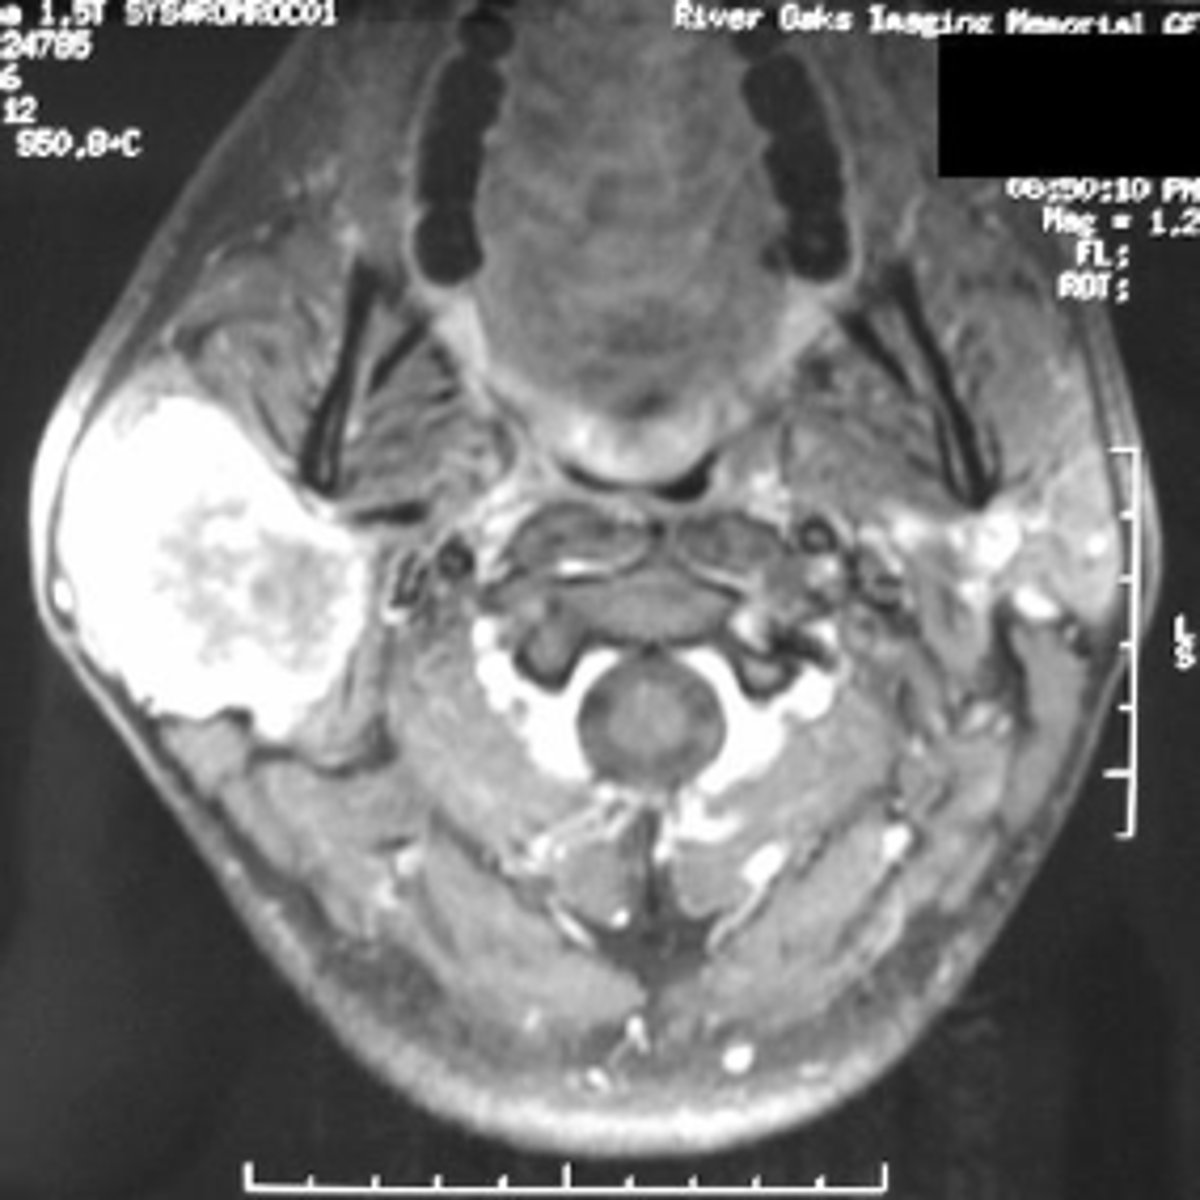

MRI

ID the type of Imaging modality:

- Pano

- CT

- CBCT

- MRI

- Technetium 99 bone scans

- PET